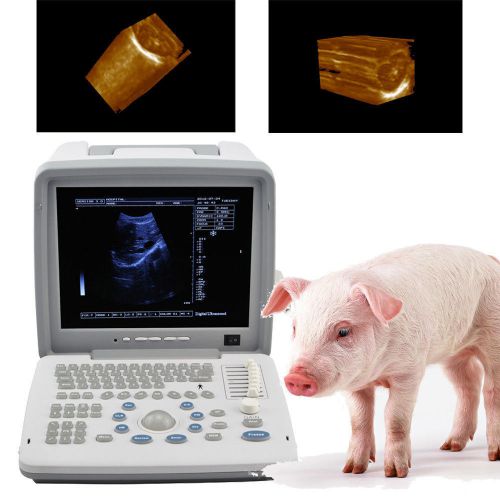

3D Portable Notebook Digital Laptop Ultrasound machine Scanner CONVEX PROBE

12.1 Veterinary VET Full Digital Portable Ultrasound Scanner linear 3D software

New 12.1 Full Digital Portable Ultrasound Scanner trans vaginal 3D workstation

3D Full Digital Portable Ultrasound Scanner convex & Transvaginal 3D workstation

12.1 LED Full Digital Portable Ultrasound Scanner rectal probe 3D workstation CE

Veterinary vet Full Digital Portable Ultrasound Scanner Rectal 3D workstation

2014 Veterinary vet Full Digital Portable Ultrasound Scanner Rectal 3D Software

NEW Diagnostic Ultrasound Scanner MACHINE +3D function + convex sensor pregnancy

2015 Digital Laptop Ultrasound Scanner+Convex+ Transvaginal Probe+ 3D image-DHL